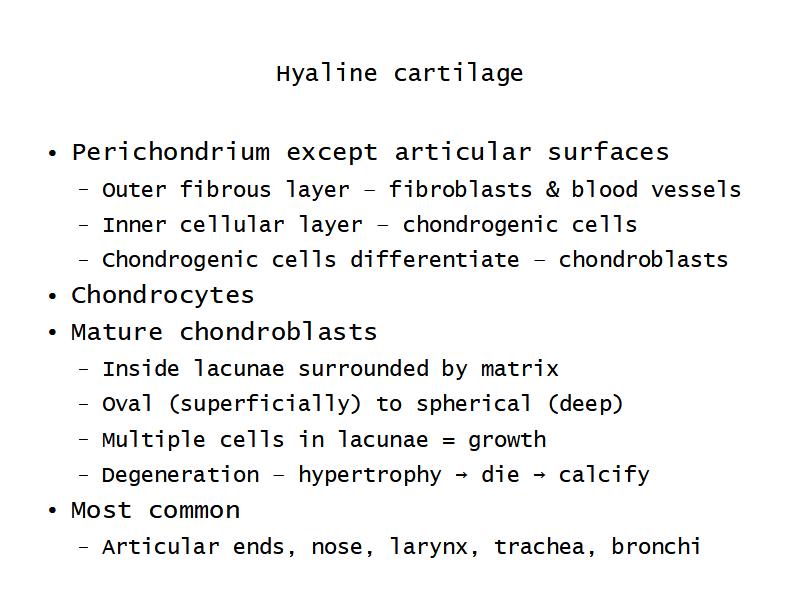

Trachea

Bronchi - Transitions

- Intrapulmonary bronchi

- Irregular cartilage

- Respiratory epithelium

- Glands